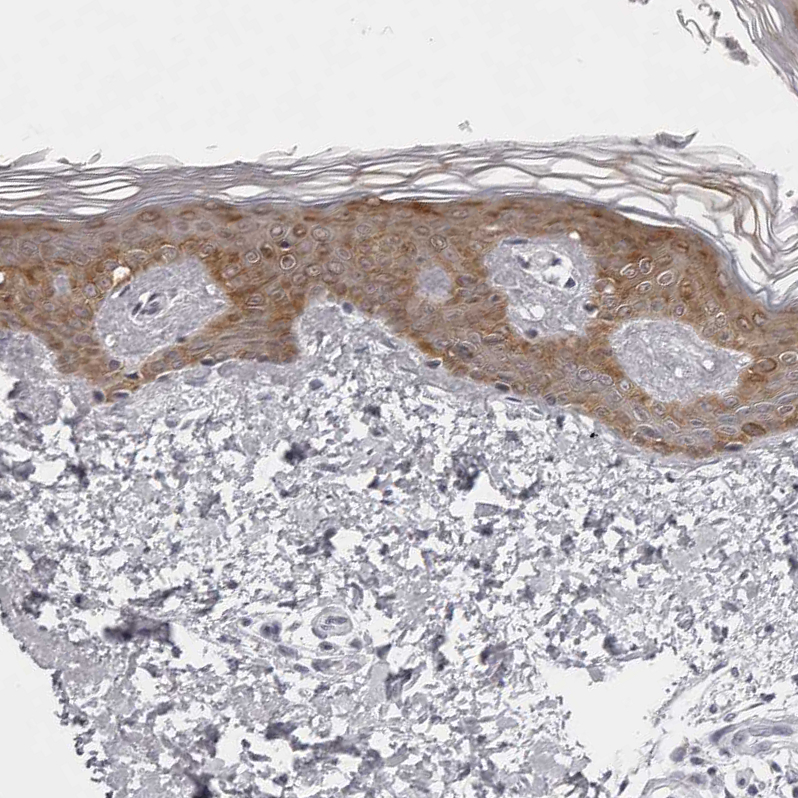

Immunohistochemical staining of human skin shows strong cytoplasmic positivity in squamous epithelial cells.